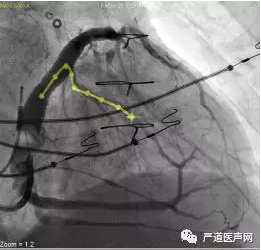

最终影像

术后讨论

➛ 右房大,左室递送系统没有支持

➛ 窦口开口高,开口方向较陡

➛ 鞘中鞘可考虑

➛ 右心导管增加支撑

➛ 撤出鞘中鞘后调整导线弧度,弧度过多,容易脱位,适当的弧度是保证撤鞘时导线稳定的前提